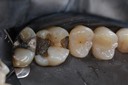

Alan Chinn #2 - 5 finish